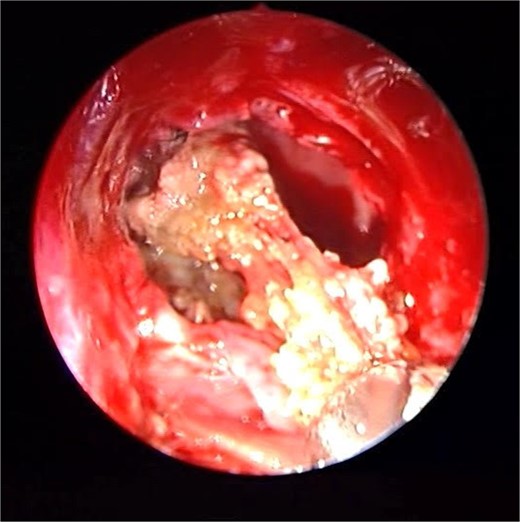

Endoscopic intraoperative view of the sphenoid sinus full of fungal mud and mucin.

Patient presented to the emergency department with four days history of sever left side headache associated with nausea and vomiting, and nasal discharge with on\off nasal obstruction. Two days history of diplopia with lateral gaze of the left eye, with decrease the visual acuity. Ophthalmologic examination revealed left abducens nerve palsy. Other neurologic examinations were within normal. Endoscopic nasal examination revealed left multiple grade two nasal polyps occupying the middle meatus. Pre-operative brain computed tomography (CT) shows bilateral near total opacification and expansion of the paranasal sinuses and nasal cavity (Fig. 1). Additionally, there is evidence of invasion of the left cavernous sinus with encasement of cavernous segment of left internal carotid artery (ICA). Furthermore, pituitary gland and optic chiasm displaced superiorly. Magnetic resonance imaging revealed that the sphenoid sinus is expanded and bulging superiorly into the pituitary fossa causing displacement of pituitary gland and stalk without mass effect upon the optic chiasm (Fig. 2). It extends laterally causing effacement of the cavernous sinus and left Meckel’s cave. No evidence of intracranial extension. The patient underwent functional endoscopic sinus surgery with computer-assisted navigation system. Intraoperatively, sphenoid sinus was full of fungal mud and mucin (Fig. 3). The polyps were removed completely from the nasal cavities, fungal mud, and mucin were removed from the sinuses (Figs 4 and 5). Patient had dramatic improvement after surgery, the rhinosinusitis symptoms are resolved, the diplopia has been improved, and the paranasal sinuses were clear. The patient was discharged with topical corticosteroid and saline irrigations.